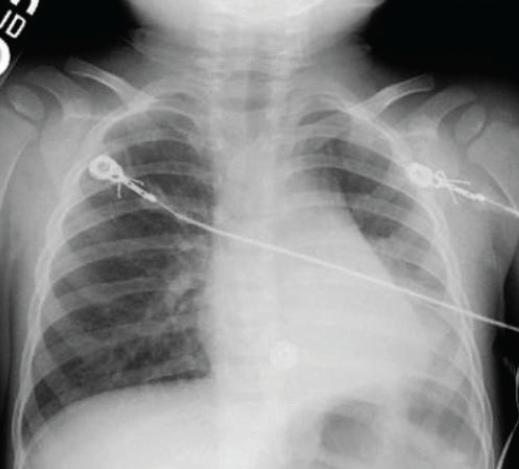

aspiration

Nishit Patel, MD; Bashar Shihabuddin, MD

<p><img src="/sites/default/files/transfer/Screen_Shot_2013-10-15_at_3.41.01_PM.png" alt="aspiration" width="115" height="115" style="float: left;...